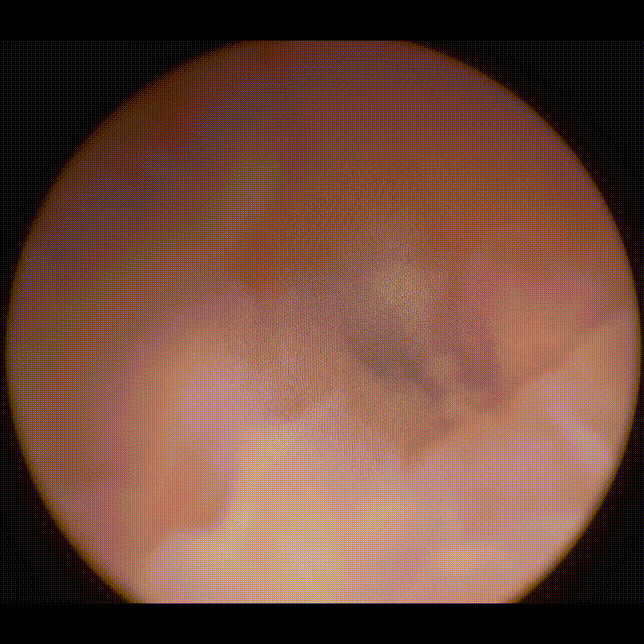

李女士术后输尿管镜检查